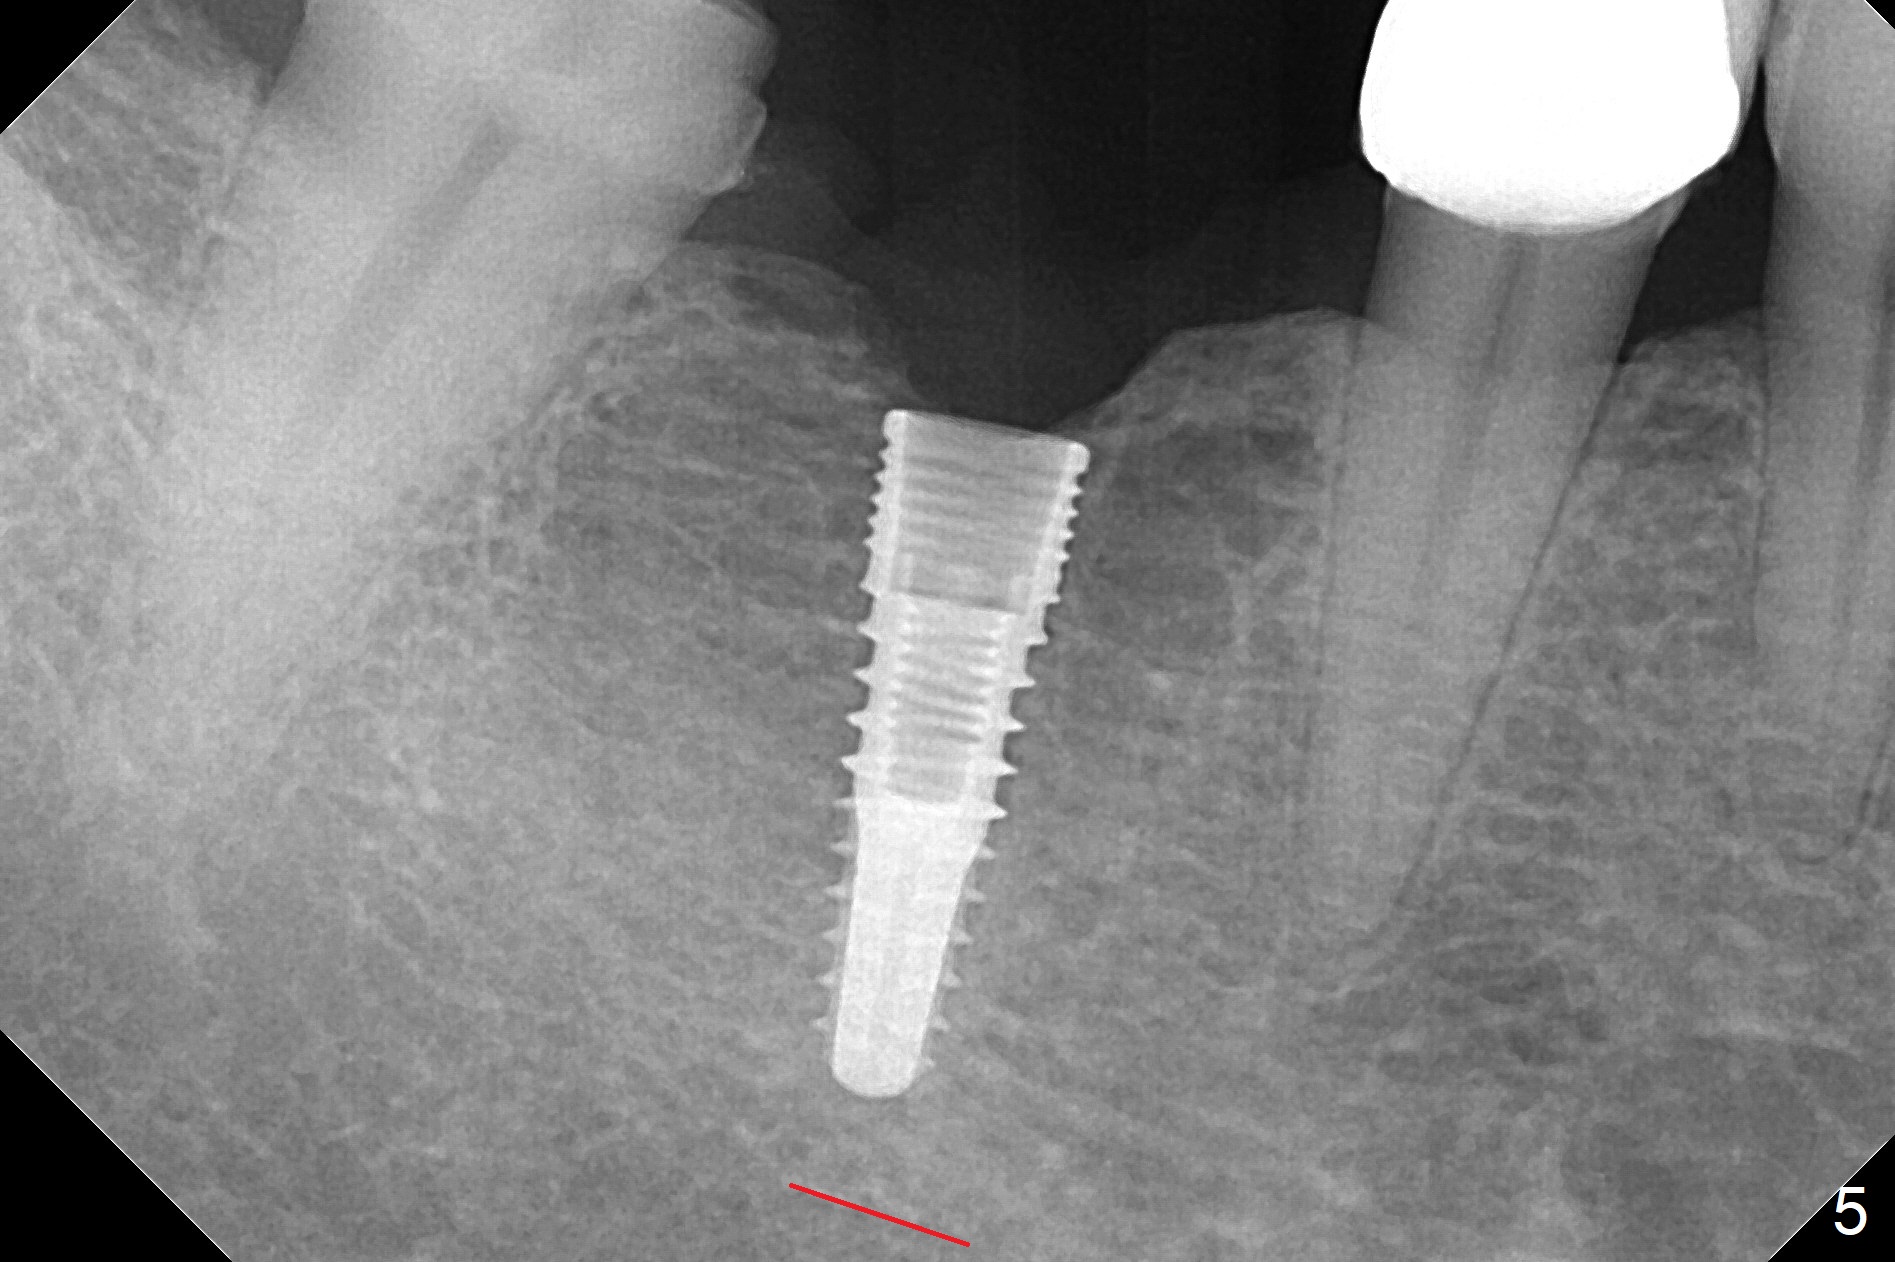

The apparently narrow ridge at #30 before bridge sectioning (Fig.1) is confirmed with incision (Fig.2). Following ridge reduction, osteotomy is initiated with 2 mm pilot drill (Fig.3). When a 3.8x12 mm SM narrow implant is placed with 40 Ncm, there is 1-2 mm cortical bone buccolingually (Fig.4,5). The thick cortices do not seem to be easy to be bent, i.e., expanded. RCT is finished at #31 one month post implant placement (Fig.6,7), the flattened ridge appears to have started to undergo remodeling. Ridge reduction makes it possible for the implant to remain subcrestal postop (Fig.4). The bone surrounding the implant may reduce the likelihood of implant fracture. The crowns at #30 and 31will be fabricated together with light occlusion at #30. In fact the splinted provisional dislodges. There appears dense bone formation 3 months postop (Fig.8 *). The drawback of using a SM narrow implant is that a narrow abutment has to be used (4.8x4(4.5) mm). The implant crown is dislodged immediately after the patient finishes lunch. Following recementation, the occlusion is reduced. In fact, UF or IBS has no such drawback: the implant could be small, but the abutment could be large. One year post cementation, the crown at #31 needs recementation (Fig.9); the bone density next to the coronal implant increases (*).